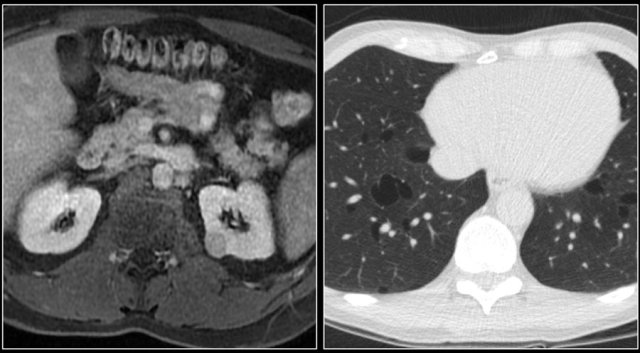

The kidney is a common extranodal site of lymphoma involvement, especially in Non-Hodgkin lymphoma.

Primary involvement of the kidney is rare.

Renal lymphoma usually presents as multiple poorly enhancing masses, but may also present as retroperitoneal tumors directly invading the kidneys or as perirenal soft-tissue masses.

Diffuse infiltration of the renal interstitium results in nephromegaly and is more common in Burkitt lymphoma.

The image shows bilateral involvement of the kidney and a bone lesion in a patient with B-cell lymphoma.

Here another patient with lymphoma located in the mediastinum, pancreas (arrow) and in both kidneys.

Diffuse enlargement of both kidneys in a patient with lymphoma.

Continue with the PET-CT.

PET-CT shows diffuse renal involvement and also positive periaortic lymph nodes (arrows).